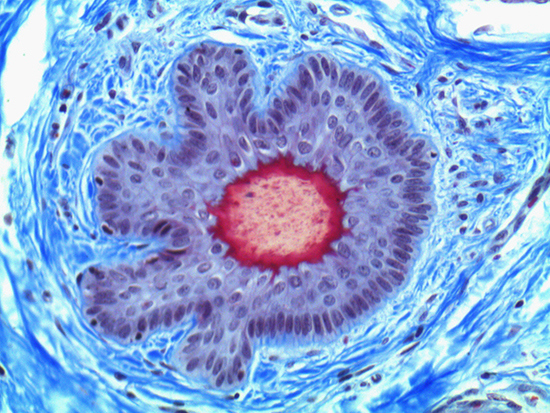

Figure 1: Brightfield Image of Dermal Tissue

When comparing Figures 1 and 2, the visual differences are significant. A brightfield image is formed with the illumination source below the sample, and then transmitted light propagates through the sample to the sensor forming a bright, white background with sharp color. A darkfield image is formed by directing light at an oblique angle through the sample, forming a hollow cone of light which is collected by the objective. Darkfield illumination typically yields a dark background with sharp color, but in the case of Figure 2, the collagen and muscle fibers interfered with the light path and caused a blur of light and color. The dark background is hardly evident and only two distinct colors are visible. When analyzing histological stains, brightfield illumination is the preferred technique for lighting a sample.

Figure 3: Brightfield Image of Dermal Tissue filtered with Green

When comparing Figure 3 with Figure 4, there is once again a significant visual difference. The most obvious feature is the change in color from green to red due to a different hardcoated filter being positioned in the optical path. The less obvious difference is the varying contrast levels caused by the filters at specific regions of the dermal tissue. For example, Figure 3 exhibits a distinct ring at the central region of the cell with additional matter within. In Figure 4, the ring is extremely faint and the internal matter is not visible. With that said, the cell and surrounding dense materials are more evident in Figure 3, whereas the muscle fibers and collagen are more pronounced in Figure 4.